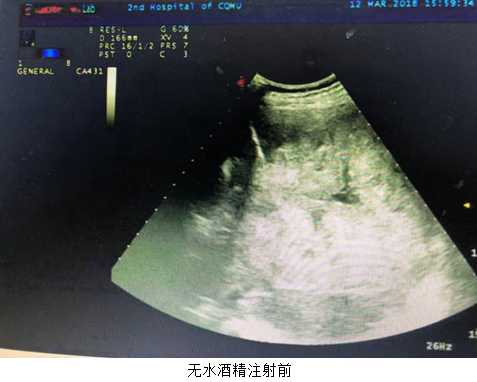

2018年3月13日,肿瘤中心蒋萱主治医师在超声引导下成功行经皮肝癌瘤内注射无水酒精1例。